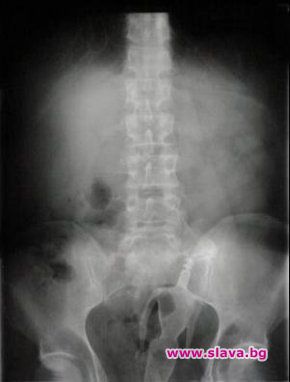

Именно в семейното жилище в областния град се разиграла драмата – дългопазената хомосексуална наклонност на даскала лъснала, когато той бил заварен в брачното ложе крещящ от болка и със стърчащи от дупето чифт кукленски крака в розови токчета. Първоначално двамата опитали сами да изтеглят кукличката от задника му, но след появата на кръв и нетърпима болка се принудили да викнат бърза помощ. Преди около година, през август 2011, лекар от Пирогов разказа и други подобни истории за заседнали странни предмети – вибратори, дезодоранти, дървени чукчета от хаванчета за чесън, шишета. Най-странно обаче било, когато дежурен екип бил посечен от реплика на младо момче: Извинявайте, но си напъхах една дюля в задника.

В повечето случаи предметите се вадят по неоперативен начин. Понякога обаче се налагат и по-сериозни мерки - например ако се окажете с флакон от пяна за бръснене в дупето и твърдите пред лекарите, че сте се подхлъзнал в банята и сте се нанизал на него, какъвто случай имаше в търновско преди време. Още по-сложна е ситуацията с дамите естествоизпитателки, търсещи всевъзможни начини да увеличат сексуалното си удоволствие.